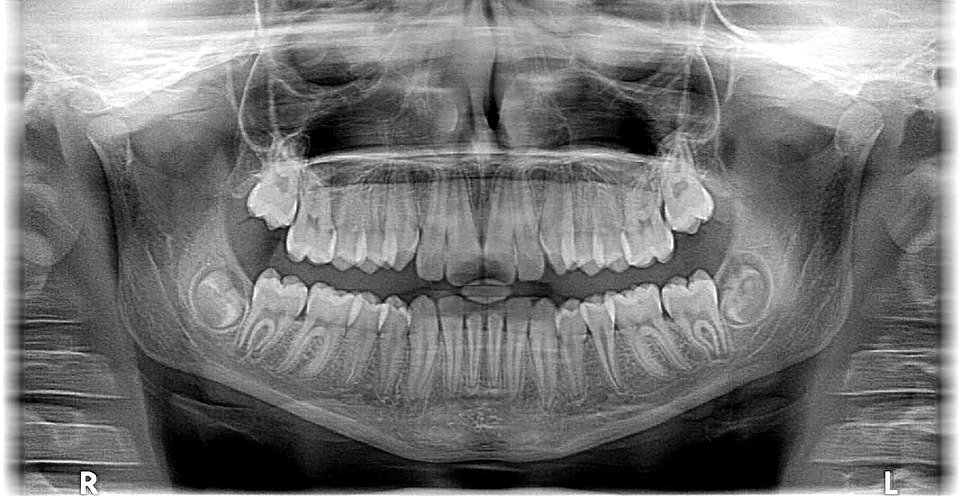

X-rays

What are the four most common images?

What are some benefits of getting preventative x-rays?

Which is safer traditional or digital x-rays?